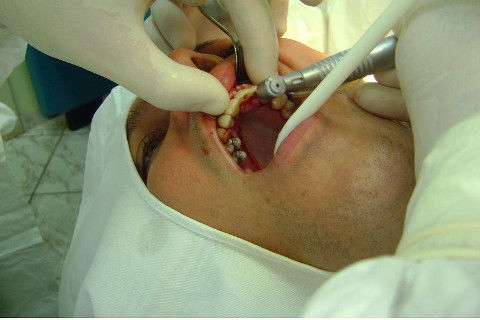

Cirurgia realizada hoje de manhã...No planejamento percebi medindo espessura do rebordo com especímetro que as medidas não estavam muito boas, ou o ideal, em torno de 4,5 a 5 mm ate´o terço médio do rebordo e melhorava no final, com 6 a 7 mm. Optei então por uma pequena expansão usando os expansores rosqueáveis. Aconteceu uma pequena fenestração na hora da fixação dos implantes, especialmente na região do 22 que fraturou o início da tábua óssea, mas não me preocupei porque não foi mais do que 2 mm de fratura em direção apical, o implante ficou infraósseo e com boa estabilidade (60 N no 21 e 40 N no 22). Esta fratura tb não deixou osso completamente solto, foi do tipo galho verde, deixei em posição e suturei normalmente. Só não fiz e nem estava planejado carga imediata mesmo, mais pelo motivo da oclusão inadequada do caso.